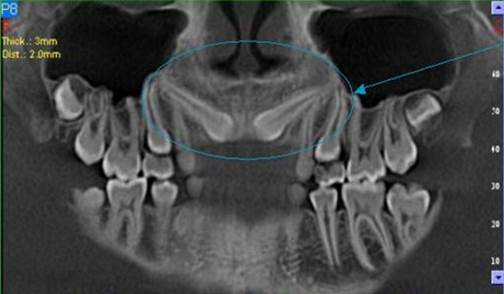

3D DVT - NewTom

Je speciální zubní digitální tříprostorový tomograf (3D), který umožňuje na základě jediného snímkování vytvořit všechny typy RTG zobrazení, které jsou pro lékaře potřebné. Díky používané technologii tzv. „kuželového paprsku“ a speciálním senzorům je výrazně zmenšená dávka záření - o více jak 80% proti klasickému CT vyšetření. To je významné zejména u dětí. Pomocí tohoto přístroje je možné zjisti skutečnou situaci v čelistních kostech pacienta tedy množství kosti - můžeme změřit skutečnou šířku i výšku kosti, i kvalitu kosti (hustotu) v místě uvažované implantace. 3D (tříprostorové) zobrazení umožňuje zvýšit prostorovou představu operatéra ještě před vlastní operací a zároveň pacientovi lépe objasnit a ukázat oblast plánovaného zavedení implantátu.

Pacient „neumí číst“ RTG snímky, ale díky 3D zobrazení vidí „svoji skutečnou čelist“ - např. jak je nízká či úzká, vidí průběh nervu nebo velikost čelistní dutiny, což mu umožní i pochopení nutnosti v některých případech provést pomocné zákroky ještě před vlastním zavedením implantátu (viz. kostní štěp, sinus lift, kostní granulát...).

Vyšetření pomocí tohoto přístroje používáme i ve stomatochirurgii (zlomeniny čelistí, zuby moudrosti, cysty, onemocnění čelistního kloubu), ortodoncii (retinované zuby, nadpočetné zuby), parodontologii atd.